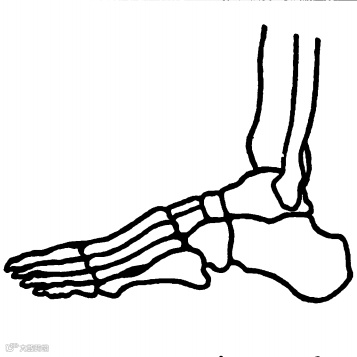

缠足过程:趾跖骨被折断,脚被紧紧地绑住数年,导致脚变短,足弓增高、畸形。

缠足的X线片显示外侧脚趾扭曲和足弓明显畸形。